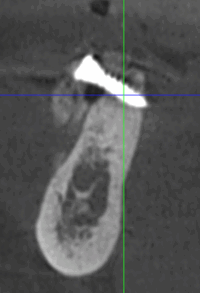

Reprise de traitement implantaire

La reprise de traitement désigne le processus par lequel un patient reprend des soins après un échec de traitement implantaire ou lorsque des complications surviennent. Voici les étapes typiques d’une reprise :

En cas d’échec ou de complications, la reprise de traitement implique une évaluation diagnostique, une extraction (si nécessaire), une cicatrisation, puis une reconstruction osseuse suivie d’une nouvelle implantation.